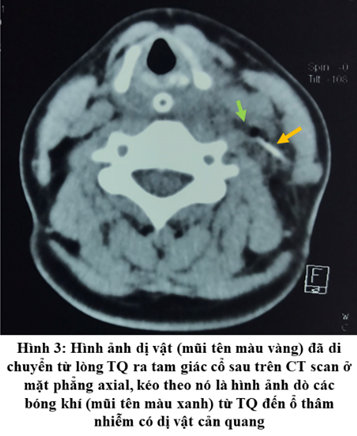

Bệnh nhân được phẫu thuật nội soi thực quản ống cứng để lấy dị vật, tuy nhiên, không phát hiện dị vật trong lòng TQ. Bênh nhân được thực hiện xét nghiệm bổ sung bao gồm siêu âm, CT scan và đã phát hiện dị vật đã di chuyển ra tam giác cổ sau. Thêm vào đó, trên đường di chuyển của mình dị vật để lại hình ảnh dò các bóng khí từ TQ đến ổ thâm nhiễm có dị vật cản quang.

Bệnh nhân đến lúc này được phẫu thuật cấp cứu mở cạnh cổ lấy dị vật, trong quá trình phẫu thuật với sự trợ giúp của siêu âm đã lấy ra được dị vật là một mảnh xương cá đường kính 2 mm, chiều dài 20 mm. Thám sát đường dò đến tận TQ hút được khoảng 10 ml dịch mủ trắng đục và tiến hành súc rửa đường dò bằng betadin. Sau đó dẫn lưu qua da đường dò và đóng vết mổ. Hậu phẫu ngày thứ 3 tiến hành để hở vết mổ 1/3 dưới mục đích chăm sóc và dẫn lưu đường dò. Bệnh nhân được xuất viện một tuần sau đó với tình trạng ổn định và sẽ được đóng đường dò thì hai sau đó.